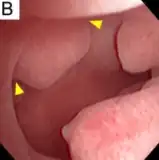

Hysteroscopy

Other tests include hysteroscopy.[2]

Pedunculated endometrial polyp

Pedunculated endometrial polyp Sessile endometrial polyp

Sessile endometrial polyp Bleeding and endometrial polyp

Bleeding and endometrial polyp Multiple endometrial polyps

Multiple endometrial polyps Multiple endometrial polyp

Multiple endometrial polyp